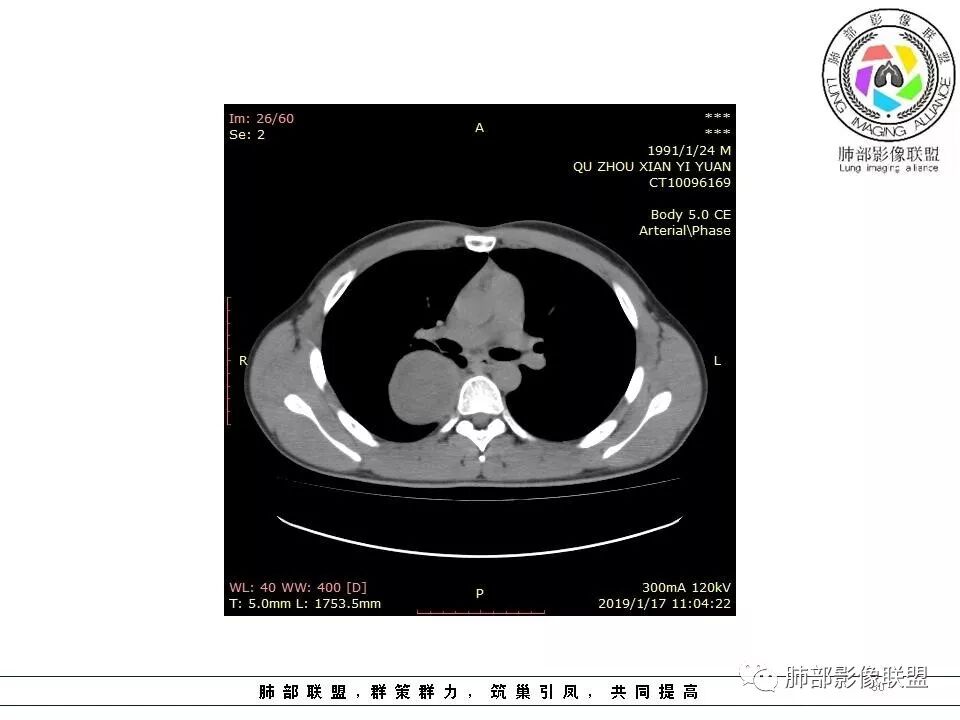

青年男性,间断胸痛;右侧脊柱旁可见一类圆形软组织密度影,密度欠均匀,增强扫描呈轻中度持续强化,邻近肺组织及肺动脉推移,可见肋间动脉供血,部分胸膜下脂肪可见,部分层面似见与右侧椎间孔相连。考虑后纵隔神经源性肿瘤。

右肺占位,跨越上叶后段、下叶背,边缘光滑,瘤肺界面清,见肺压缩缘(线样不张`强化),见胸膜尾征,胸膜下脂肪未见明显增厚,肋骨丶脊柱未见侵袭及受压,渐进性丶地图样强化,冠状位似见体循环供血

岁月:

1.右上胸内脊柱旁类圆形肿块,质地似乎比较坚实,密度稍显不均,但未显示明确的坏死。

3.相邻椎间孔未见扩大,也未见块影延入椎管,易起自于神经根的鞘瘤似乎找不到支持点。

4.静脉期轻度不均匀强化,注意不是环形强化,亦未见明确的“AB区”,这点也不支持神经鞘瘤。临床及病灶轻度强化都不支持副节瘤。